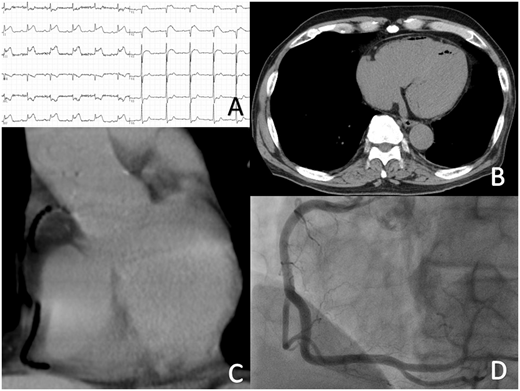

今回は循環器関連の珍しいClinical PictureがAcceptされました。

症例は「Air embolism & CT guided lung biopsy」です。

タイトルから簡単に想像がつくと思いますが本症例はCTガイド下肺生検中に冠動脈に空気塞栓が起こり、一過性の心電図変化と左室及び冠動脈内の空気をとらえたものになっています。

特に冠動脈に迷入した空気を単純CTで捉えており、まるで造影しているかのような画像は一見の価値があります。本来は検査中の事故であるためあまり胸を張って言えることでもないんでしょうが、患者さんにも大きな後遺障害などなく、無事に原疾患の治療も完了できたことから上級医と相談して投稿を決めました。

雑誌は今回も英国内科学会の発行する内科系雑誌「Quarterly Journal of Medicine(IF 3.1)」です。

元記事のリンクはこちら(追記:2017年10月20日)